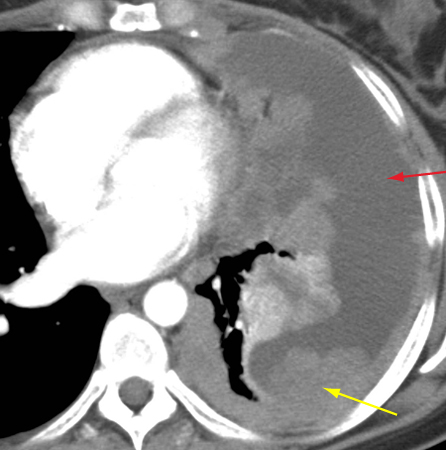

Tomografia computadorizada (TC) do tórax mostrando timoma em estádio IVA de Masaoka-Koga com derrame pleural (seta vermelha) e vastas metástases pleurais (seta amarela) juntamente à parede torácica posterior

Do acervo de Cameron Wright, MD; usado com permissão